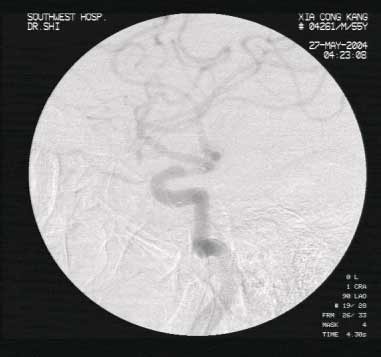

超选择性动脉内靶向溶栓典型病例:男性,56岁,以突发左侧肢体无力伴麻木6小时入院。查体左上肢肌力1级,左下肢3级,左侧偏身痛觉减退。溶栓治疗后10分钟患者左上肢肌力恢复至3级,次日左侧肢体肌力完全恢复正常,左侧偏身感觉障碍消失。